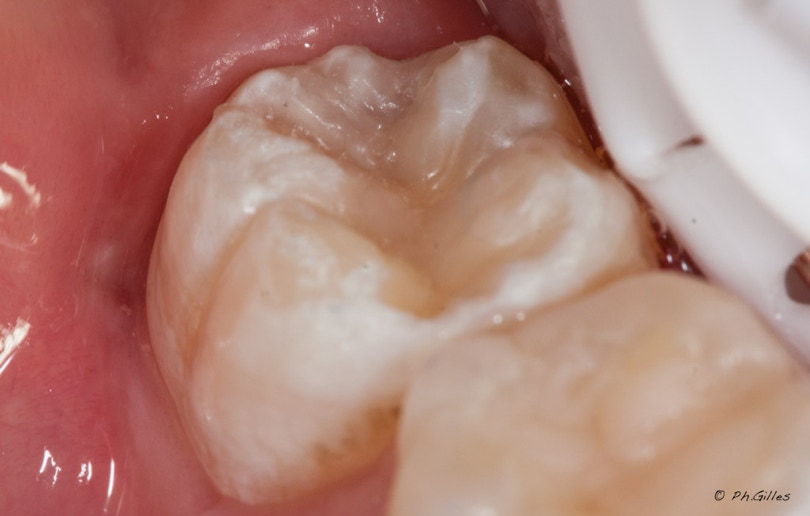

Avant - Détecteur de carie - Après